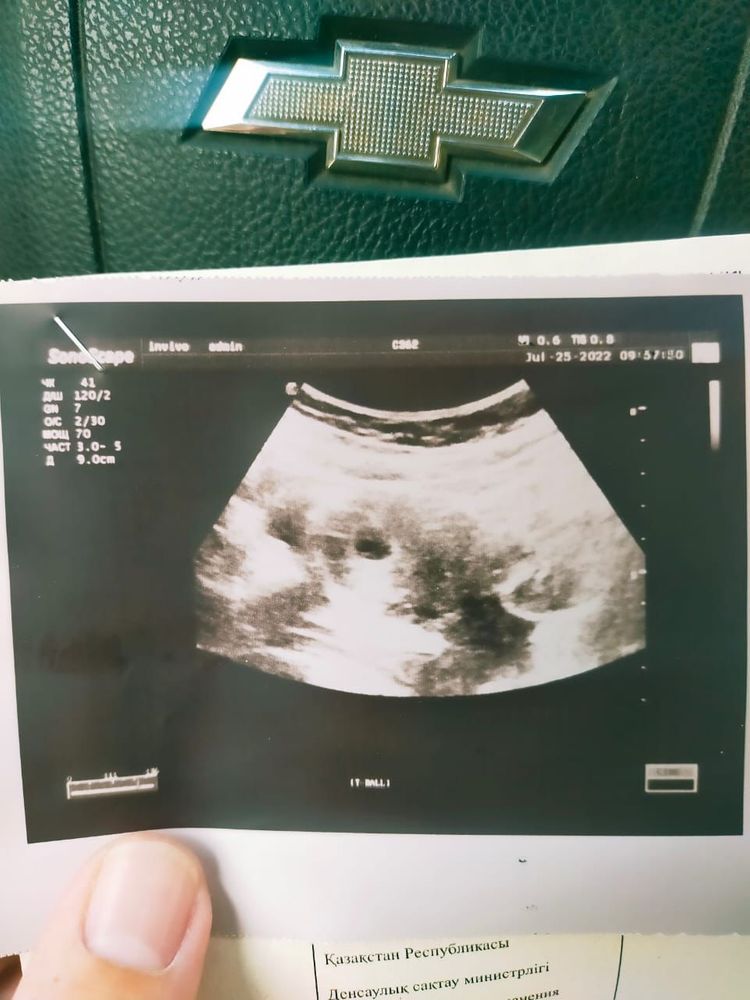

Дд.Пожалуйста, посмотрите на снимок.Можете обьяснить простым языком.Я в другой стране, где проблемы с медициной.Спасибо, заранее

Ханифа Гелдивна, если М последние 11.06. то должно быть по УЗИ примерно 6 недель, Вам поставили 5 недель, такое может быть из-за поздней овуляции, если не будет беспокойных симптомов, резких болей и кровянистых выделений, переделайте УЗИ через 1-1,5 недели. Ближе к 7 неделе должны услышать сердцебиение.